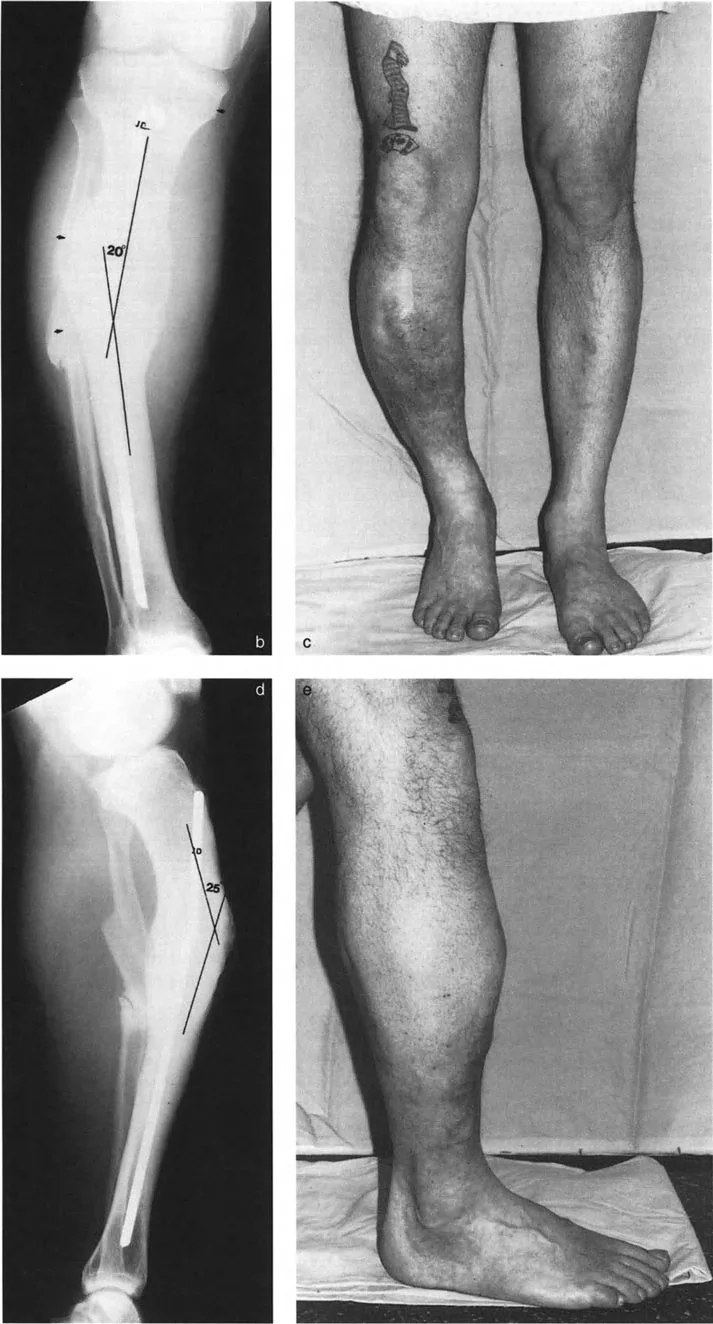

تشوهات المستوى المائل بزاوية 90 درجة

هنا، تحدث التشوهات في مستويين مائلين غير تشريحيين، لكنهما متعامدان (بزاوية 90 درجة) على بعضهما البعض. تظهر الأشعة السينية الأمامية والخلفية (AP) والجانبية (LAT) انحرافًا وانزياحًا. العلامة المميزة هي أن مركز دوران الانحراف (CORA) يقع في مستويات مختلفة على الأشعة السينية الأمامية والخلفية (AP) والجانبية (LAT)؛ أحدهما قريب من الكسر والآخر بعيد عنه.

يمكن أن تظهر الأشعة السينية المائلة، التي تُؤخذ عموديًا على مستوى أقصى انحراف، انحرافًا بدون انزياح. وبالمثل، تظهر الأشعة السينية المائلة الأخرى، العمودية على مستوى أقصى انزياح، انزياحًا بدون انحراف. في هذه الحالة، يكون مركز دوران الانحراف (CORA) على الأشعة المائلة التي تظهر أقصى انحراف عند مستوى الكسر.

مثال: التئام خاطئ لعظم الساق الأيسر يظهر انحرافًا وانزياحًا في مستويين مائلين مختلفين ومتعامدين.

تظهر الأشعة السينية المائلة في هذه الحالات أن في مستوى أقصى انحراف لا يوجد انزياح، وأن في مستوى أقصى انزياح لا يوجد انحراف. وهذا يؤكد تعامد المستويين.